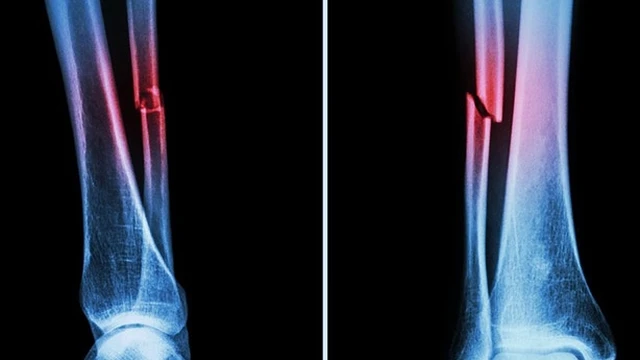

:format(webp)/gay_xuong_mac_1_Cropped_3b08c640bf.jpg)

Gãy xương mác là tình trạng chấn thương nghiêm trọng thường xảy ra ở phần cẳng chân. Chấn thương này cần được xử lý và điều trị nhanh chóng để hạn chế những ảnh hưởng liên quan quá trình vận động về sau. Nhiều người lo lắng việc để xương mác lành như ban đầu sẽ gặp nhiều khó khăn. Vậy gãy xương mác bao lâu thì lành. Cùng Nhà thuốc Long Châu tìm hiểu bạn nhé!